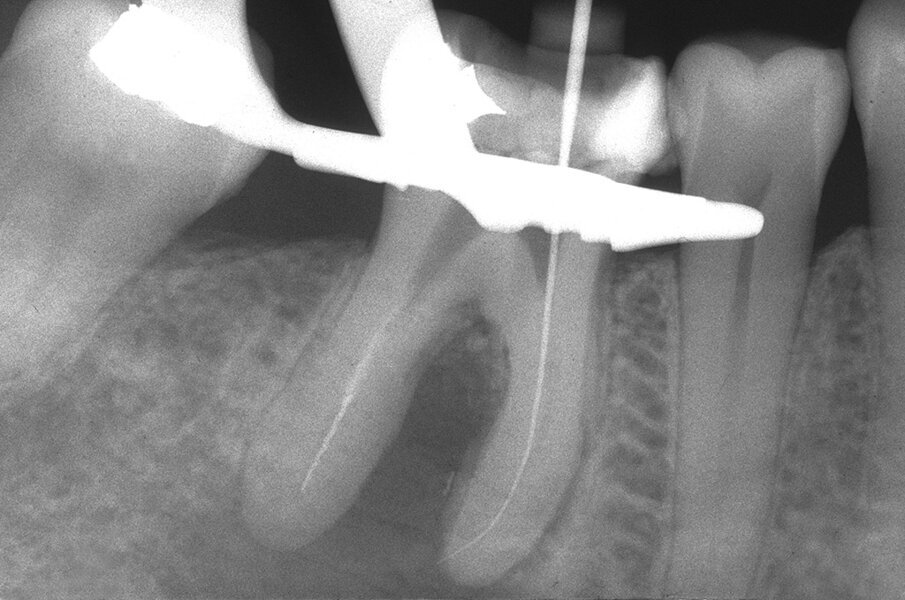

Queste perforazioni possono avvenire nel corso della strumentazione di canali curvi, per l’esecuzione del cosiddetto “trasporto esterno” del forame apicale. Una volta eseguita la perforazione, se l’operatore riesce a ritrovare e preparare il canale originale (con l’utilizzo di strumenti sottili e precurvati, molta irrigazione e soprattutto molta pazienza), il danno provocato dalla perforazione sarà minimo in quanto, soprattutto se la perforazione è piccola, si comporterà come un piccolo canale laterale che sarà facilmente otturato. Se invece il canale originale è rimasto intasato dai detriti di fango dentinale e gli strumenti ogni volta ripercorrono il cammino della perforazione, in tale caso il canale deve essere otturato con le metodiche tradizionali e successivamente l’apice contenente la porzione non trattata del canale radicolare deve essere rimosso per via chirurgica, soprattutto se stiamo trattando un dente necrotico o se siamo di fronte ad un ritrattamento (Figg. 1a-1e).

Le perforazioni del terzo medio avvengono nella maggior parte dei casi durante la preparazione della cavità d’accesso o, più spesso, durante le fasi di detersione e sagomatura o infine durante la preparazione dello spazio per un perno con l’utilizzo di frese tipo Largo, Peeso, Gates Glidden o simili (Figg. 2a-2f).